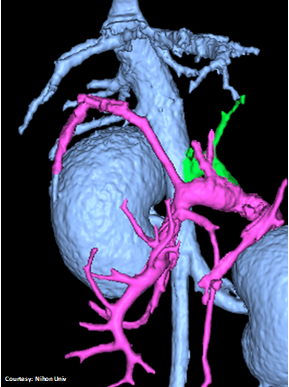

PRE-HEPATIC ENTRANCE

(GSV present)

“LGC +RGV +SGV”

Left Gastro-Caval Shunt with Right Gastric Vein and Short Gastric Vein contributions

Courtesy: Nihon Univ

WEISSE 2022